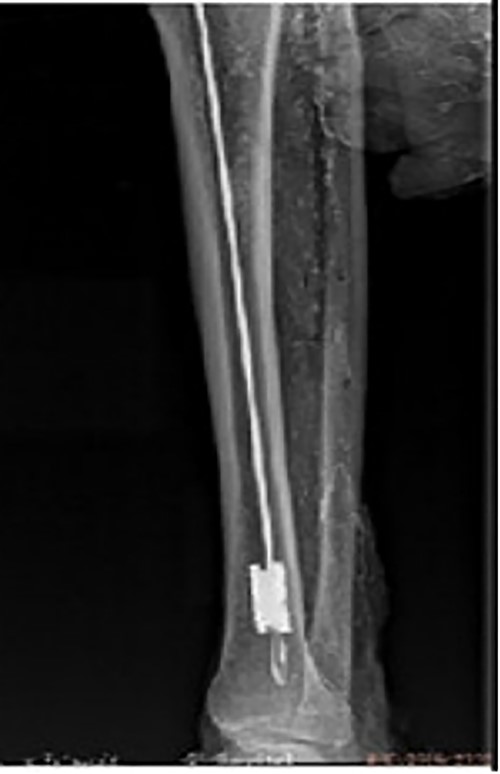

Preoperative X-ray films showing union of the right tibial fracture associated with a broken intramedullary nail remaining distal to the tibia.

A 48-year-old male patient was admitted for requesting removal of all internal implants in his body. He had a closed tibial shaft fracture caused by a collision 15 years prior and was treated with close reduction and intramedullary nailing fixation. Delayed healing occurred after the operation. A nail was broken at a distal locking screw hole. The fracture healed after plaster fixation for 3 months. The internal implant was removed 3 years after the fracture, but the distal end of the broken intramedullary nail could not be removed by the hook removal method and remained in the medullary cavity (Fig. 1). Both operations were performed in another hospital. One year prior to admission, the patient underwent open reduction and internal fixation in our hospital due to a fracture of the right distal radius, and the fracture healed after the operation. His function in the lower and upper limbs recovered well. It can be seen from the preoperative X-ray film that the remaining intramedullary nail was hollow; through measurement, it was known that the outer diameter of the broken nail was 10 mm, which was larger than the isthmus of the medullary cavity.